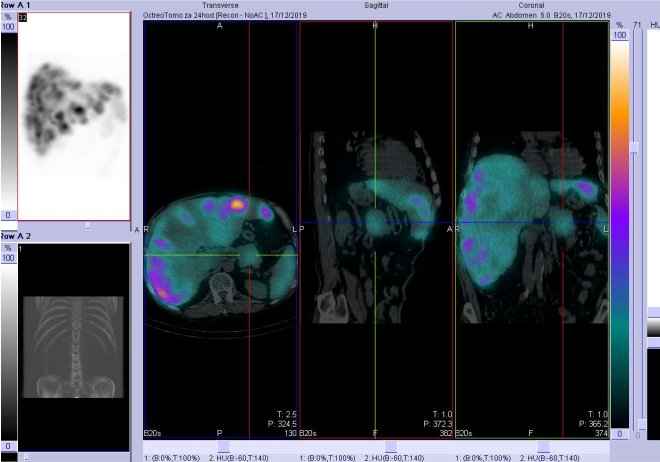

/ Obr. č. 6: Fúze SPECT/CT 24 hod. po aplikaci OctreoScanu. Zaměřeno na jaterní ložisko.

/

Prokazujeme obrovské množství ložisek se zvýšenou hustotou somatostatinových receptorů v obou jaterních lalocích a v kaudě pankreatu velikosti cca 5,6x5,8 cm.

Na ldCT velký počet hypodenzních ložisek v játrech.

Závěr: U 56letého muže scintigraficky prokazujeme mnohočetná ložiska se zvýšenou denzitou somatostatinových receptorů v játrech a jedno ložisko v kaudě pankreatu.